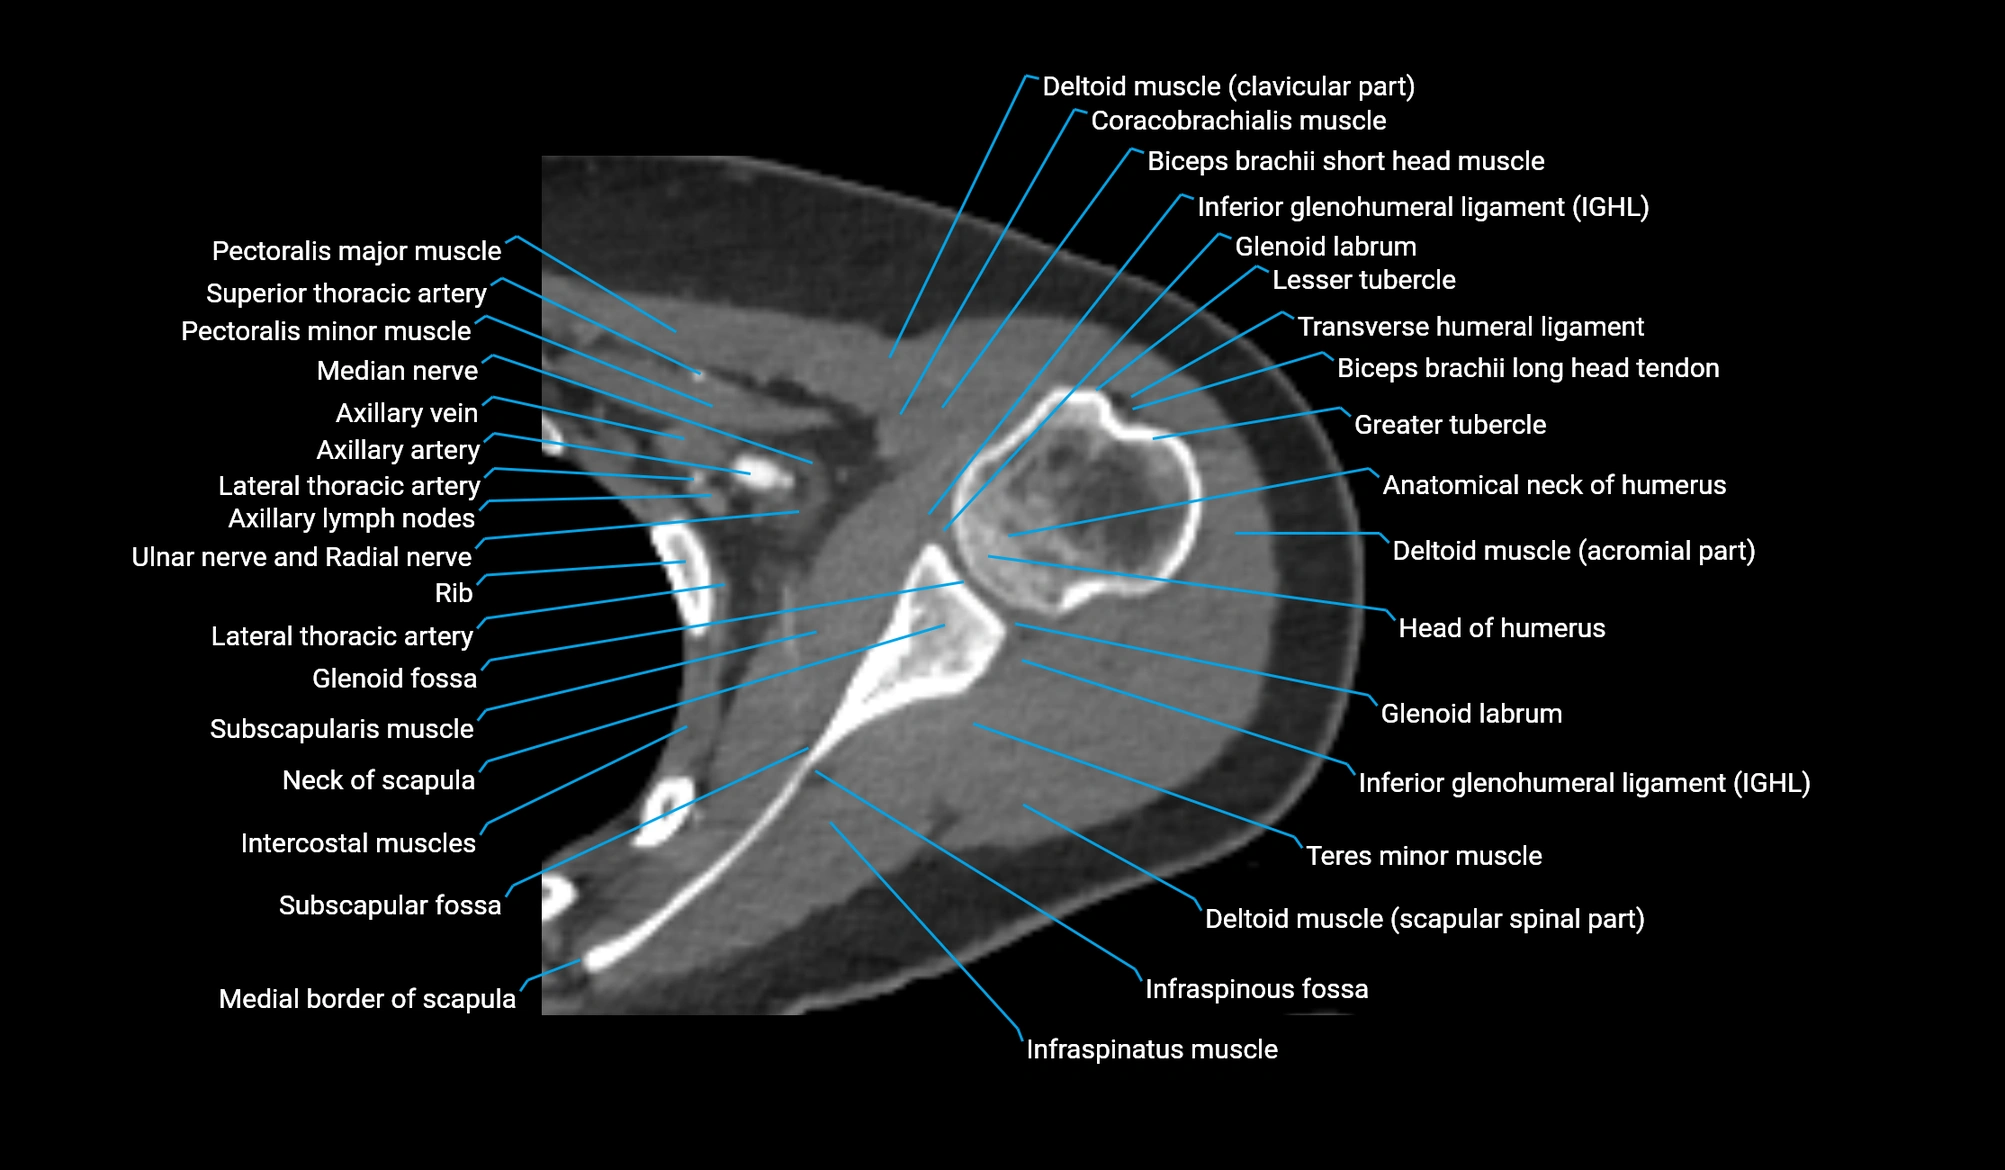

CT image